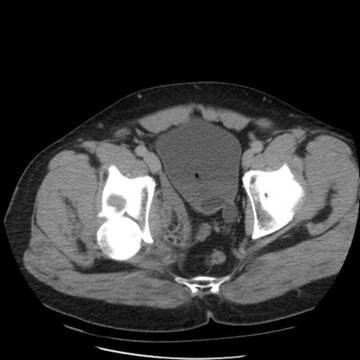

8

Q

What pathology is seen here?

A

Ectopic Kidney